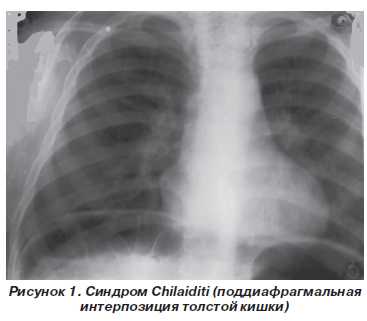

При рентгенографии органов грудной клетки под правым куполом диафрагмы определялось скопление газа с характерной для толстой кишки гаустрацией и нормальные, четкие контуры купола диафрагмы (рис. 1). УЗИ позволяло определить положение печени, ее смещение, а порой и ротацию, наличие перистальтики в отделе толстой кишки, внедрившейся в правое поддиафрагмальное пространство.

Несмотря на информативность рентгенологических и сонографических данных синдрома Chilaiditi, необходимо проводить дифференциальную диагностику с поддиафрагмальным абсцессом, скоплением свободного газа при перфорации полого органа, диафрагмальной грыжей. Различают бессимптомное течение ИТК при перемежающейся форме, когда кишка периодически самопроизвольно уходит из-под диафрагмы. Перемежающуюся форму ИТК мы чаще всего встречали у детей с бронхолегочной патологией. При постоянной форме ИТК (чаще на фоне абдоминальных причин) толстая кишка остается всегда интерпозицированной, вызывая при этом клинику кишечной непроходимости, которую мы наблюдали в двух случаях. У одного больного ее удалось разрешить консервативно, другой ребенок был оперирован. Приводим выписку из истории болезни оперированного нами пациента.